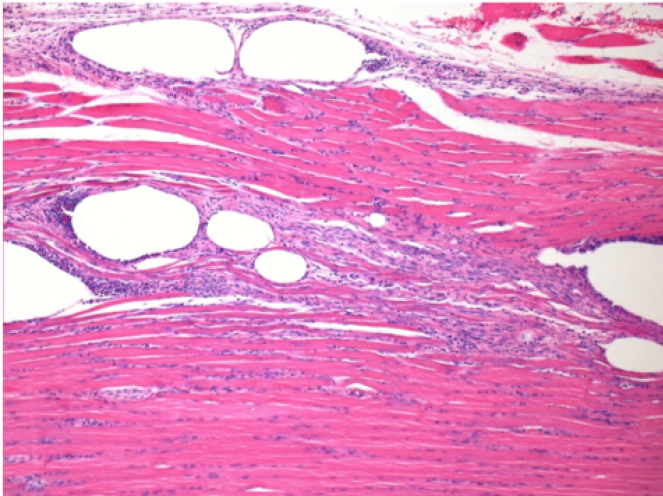

10 Inyección subcutánea

0,5 ml (5 x 0,1 ml) Endopeel SC Inyección en el área pretibial subcutánea derecha.

L:200x-Control-SC

R-D10-SC-200X

R-D30-SC-200X

R-D90-SC-200X

R-D210-SC-200X

R-D210-SC-400X